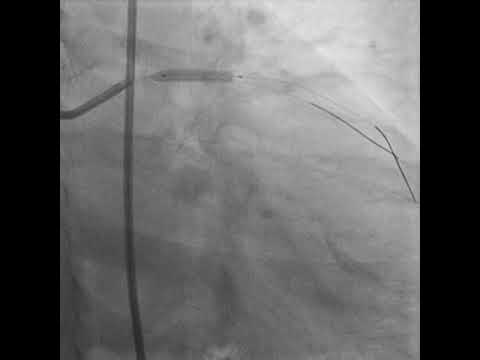

PROVISIONAL STENTING OF LAD - D1 BIFURCATION